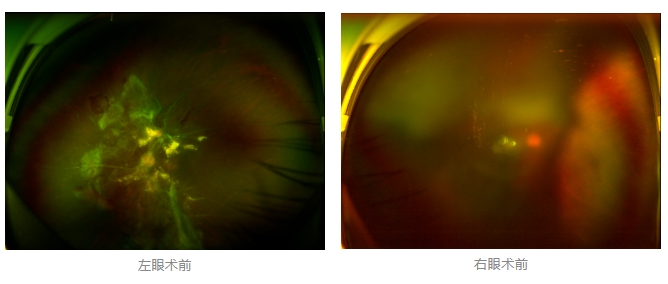

經(jīng)廈門眼科中心眼底病??菩姓魅瓮鯐圆z查后,確診其雙眼糖尿病視網(wǎng)膜病變VI期,伴發(fā)雙眼視網(wǎng)膜脫離和黃斑水腫,且右眼視網(wǎng)膜上增殖膜叢生,若再不盡快進(jìn)行治療,恐有失明風(fēng)險(xiǎn)。

面對陳先生的復(fù)雜病情,王曉波主任采用玻璃體切割術(shù)聯(lián)合膜切除術(shù)等方式,精細(xì)剝離牽拉視網(wǎng)膜的增殖膜,復(fù)位脫離的視網(wǎng)膜,同時(shí)進(jìn)行玻璃體腔注藥促進(jìn)黃斑水腫吸收。

經(jīng)過規(guī)范化治療,術(shù)后2個(gè)月復(fù)查時(shí)陳先生的視力已有明顯改善,矯正視力從眼前指數(shù)提升至0.3,成功擺脫“失明危機(jī)”。但王曉波主任強(qiáng)調(diào):“這只是階段性勝利,后續(xù)治療不能松懈。”